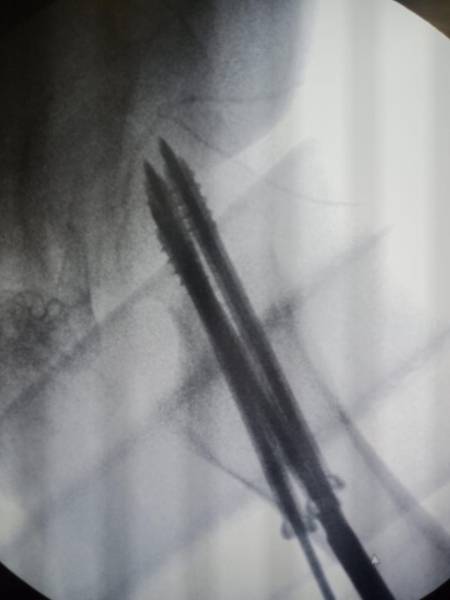

- إجراء عمليات جراحية معقدة و دقيقة في مجال العظام و المفاصل و الكسور و الإصابات ، رغم الضغط الكبير على المستشفى و أعداد المراجعين الكبيرة.

- تطبيق تقنيات جراحية حديثة و متقدمة، و ذلك في ظل التحديات التي يواجهها الفريق بسبب أعداد المرضى و المراجعين الكبيرة.